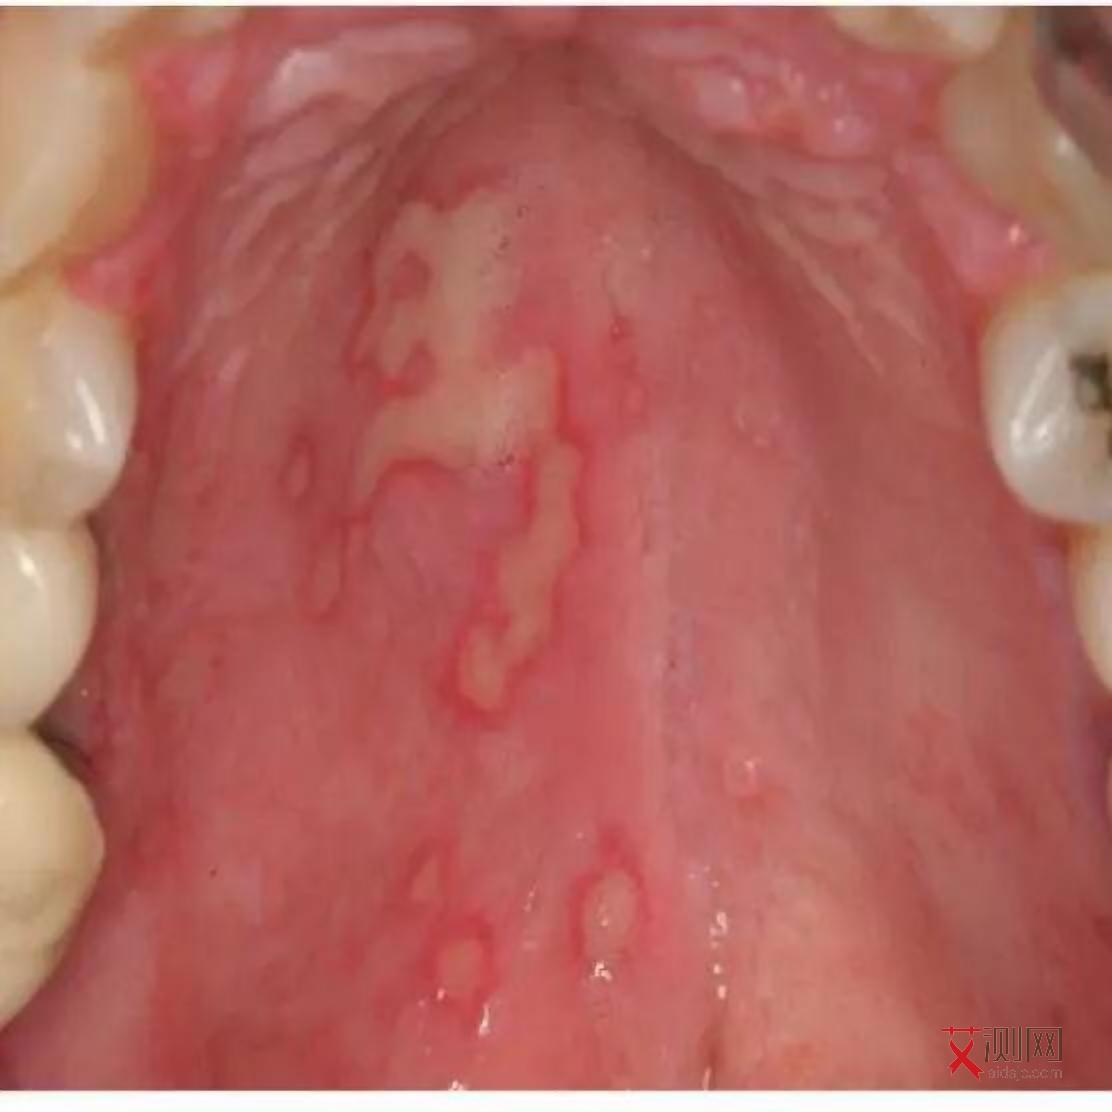

- 消化系统:可能出现严重的腹泻,每天排便次数增多,可能达到数十次,大便呈水样或稀便,伴有腹痛。长期腹泻会导致患者身体消瘦、营养不良,体重明显下降。还可能伴有口腔念珠菌感染,口腔黏膜出现白色的斑块,不容易擦去,擦去后可能会露出红色的创面,伴有疼痛,影响进食。

- 卡波西肉瘤:这是一种较为常见的与艾滋病相关的肿瘤。多发生在皮肤和黏膜部位,表现为紫色或暗红色的斑块、结节,形状不规则,边界可能不太清晰。常见于面部、口腔、生殖器等部位。